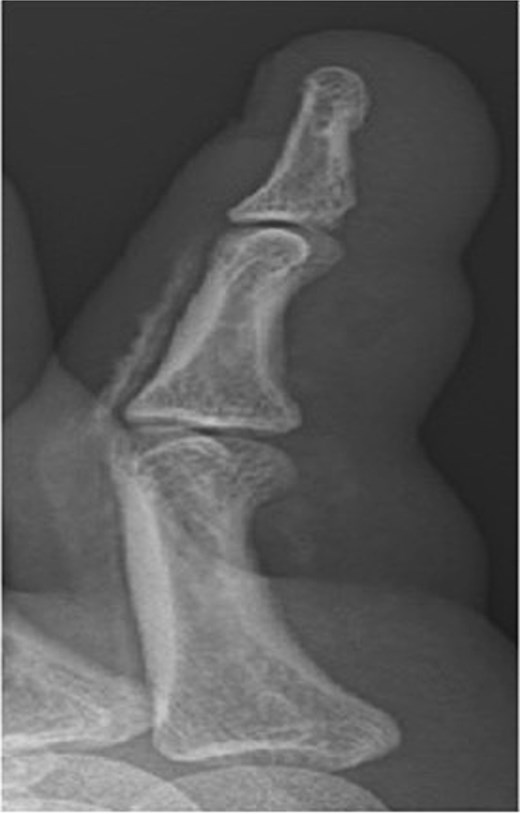

X-ray image of patient one showing injected material into volar surface of his digit.

X-ray image of patient three showing injected material into surface of his digit, more obvious in the proximal portion.